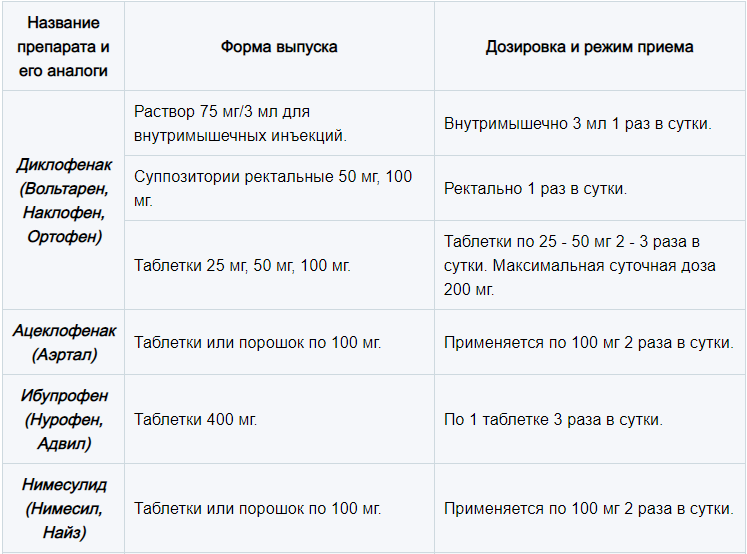

Артроз голеностопного сустава 2 степени схема лечения